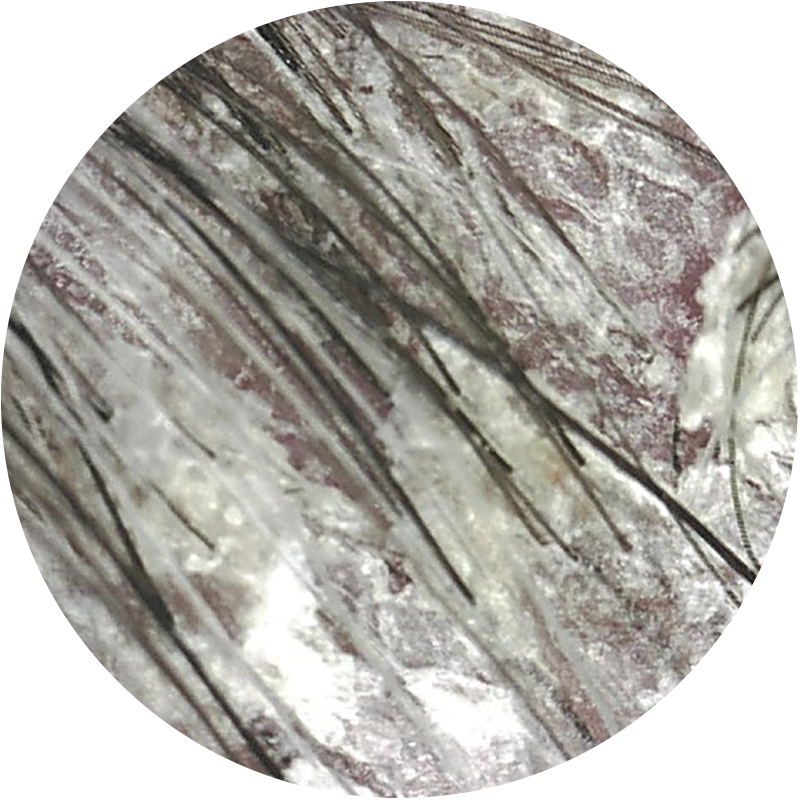

Visión Cámara Tricoscópica

ANTES

Alopecia androgenética

3 meses de tratamiento